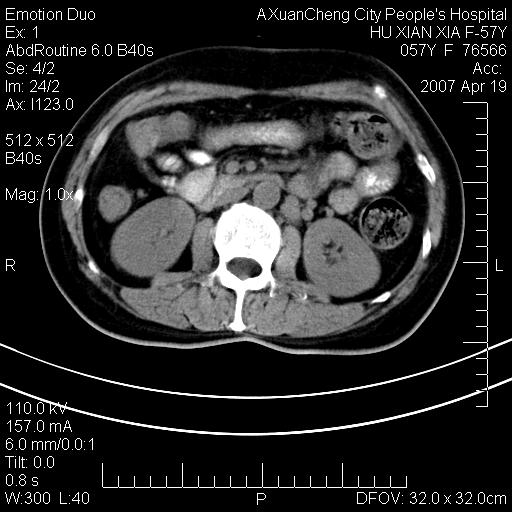

标题: CT7778:[原创]F,57Y腹痛待查,胸片提示肺部占位,应当很典型 [打印本页]

标题: CT7778:[原创]F,57Y腹痛待查,胸片提示肺部占位,应当很典型

胸片提示肺部占位

考虑双侧肾上腺占位

双肾上腺占位

双侧肾上腺及腹膜后淋巴结增大,考虑转移,建议查原发灶.

双侧肾上腺转移瘤?

双侧肾上腺增大,有分叶,密度均匀,考虑转移建议查原发灶

双侧肾上腺及腹膜后淋巴结增大,考虑转移,肺转移?

双侧肾上腺结节样肿块,结合肺部肿块,考虑肺癌肾上腺转移。

双侧肾上腺及腹膜后淋巴结增大,结合胸片提示肺部占位,考虑肺癌双侧肾上腺及腹膜后淋巴结转移.